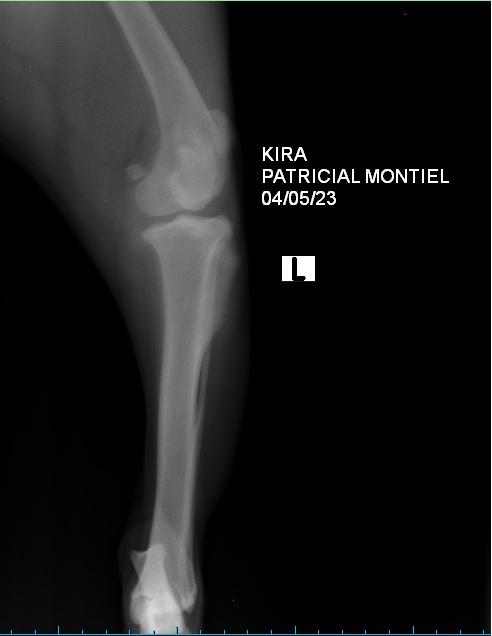

Identificado el dolor en la rodilla, debemos trasladar a nuestro perro al veterinario, quien podrá diagnosticar la rotura realizando un examen físico mediante palpación de la rodilla, como con la denominada prueba del cajón. Además, con una radiografía podrá valorar el estado de los huesos de la rodilla. Los datos que le aportemos también ayudarán al diagnóstico, por eso debemos informarle de cuándo ha aparecido la cojera, cómo es esta, si remite con el reposo o no o si el perro ha sufrido algún golpe reciente. Debemos saber que es característico de la rotura de ligamento cruzado en perros que comience con mucho dolor, que va a remitir hasta que la rotura afecte a toda la rodilla, momento en el que vuelve el dolor por los daños consecuencia de la rotura, como la artrosis.